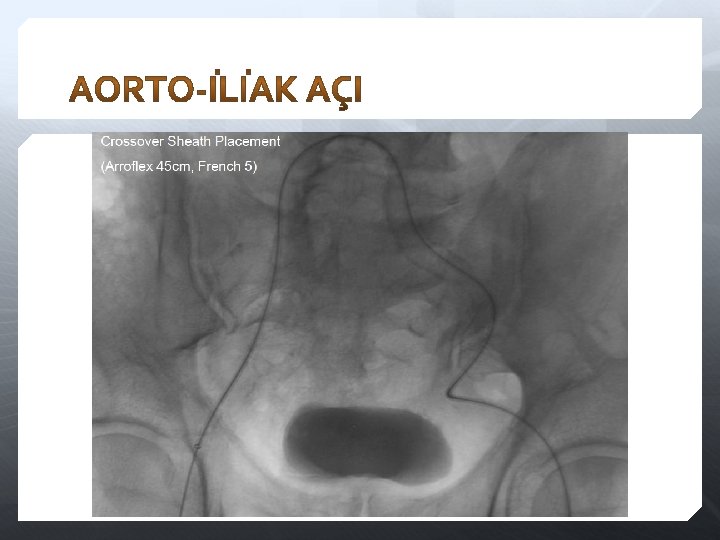

Aorta-İliak

0. 035’/0. 018’ kılavuz tel Lezyon geçmek için hidrofilik CTO wire Cross-over için uzun ve sert 4 F-7 F sheath 4 F-5 F kateter (Cobra, SIM 1, RDC, Sos-Omni, Vertebral, Bern, vb) Hidrofilik Sert Kılavuz Sheath Lümen heparinli serum ile yıkanır